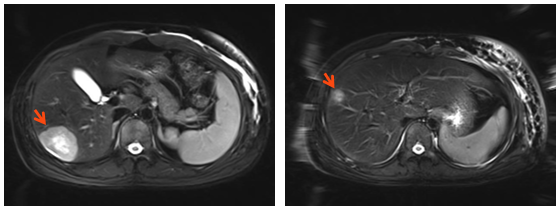

4.肝增强MRI:S6段 、S7段可见强化结节,小者长径为1.4cm(靶病灶3),大者为长径4.3cm(靶病灶4)。(图4)

图4 肝增强MRI

3.靶病灶3、4(肝转移病灶)评效:2周期部分缓解PR,4-8周期病灶持续缩小,维持PR。(图9)

图9 靶病灶3、4(肝转移病灶)评效PR